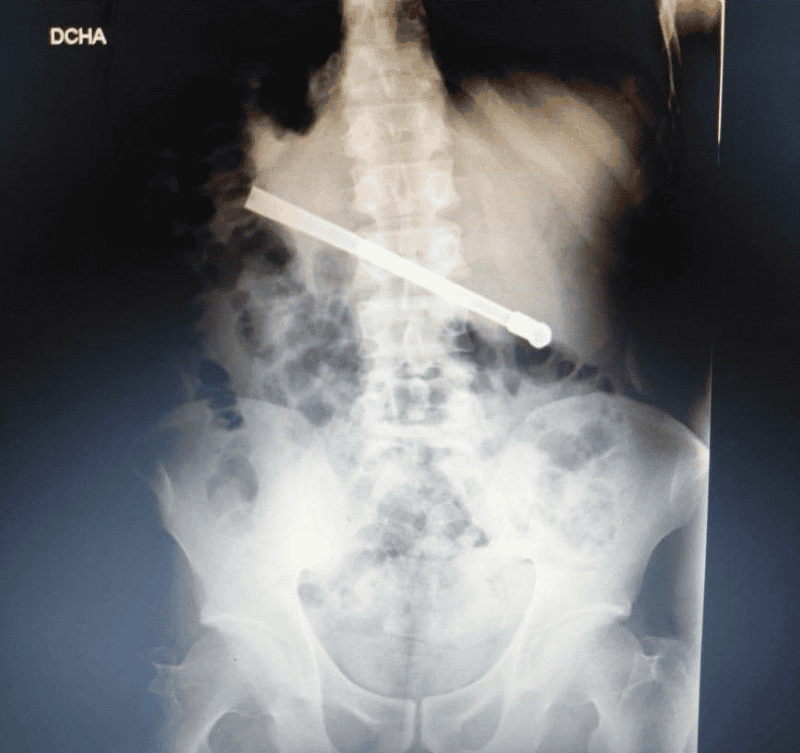

Al continuar con el malestar, le realizaron una placa radiográfica en la Unidad Penitenciaria ubicada en 27 de febrero al 7800, y pudieron determinar que había ingerido una bombilla de mate que quedó alojada transversalmente en la cavidad torácica.